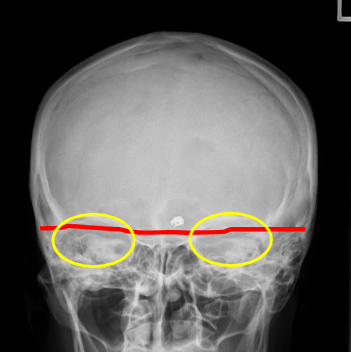

Q

what should be corrected about the petrous ridges in this PA cadwell

A

nothing!

what are the corrections for this PA caldwell (3)

CP needs to be raised

nose to go right slightly

vertex to go left